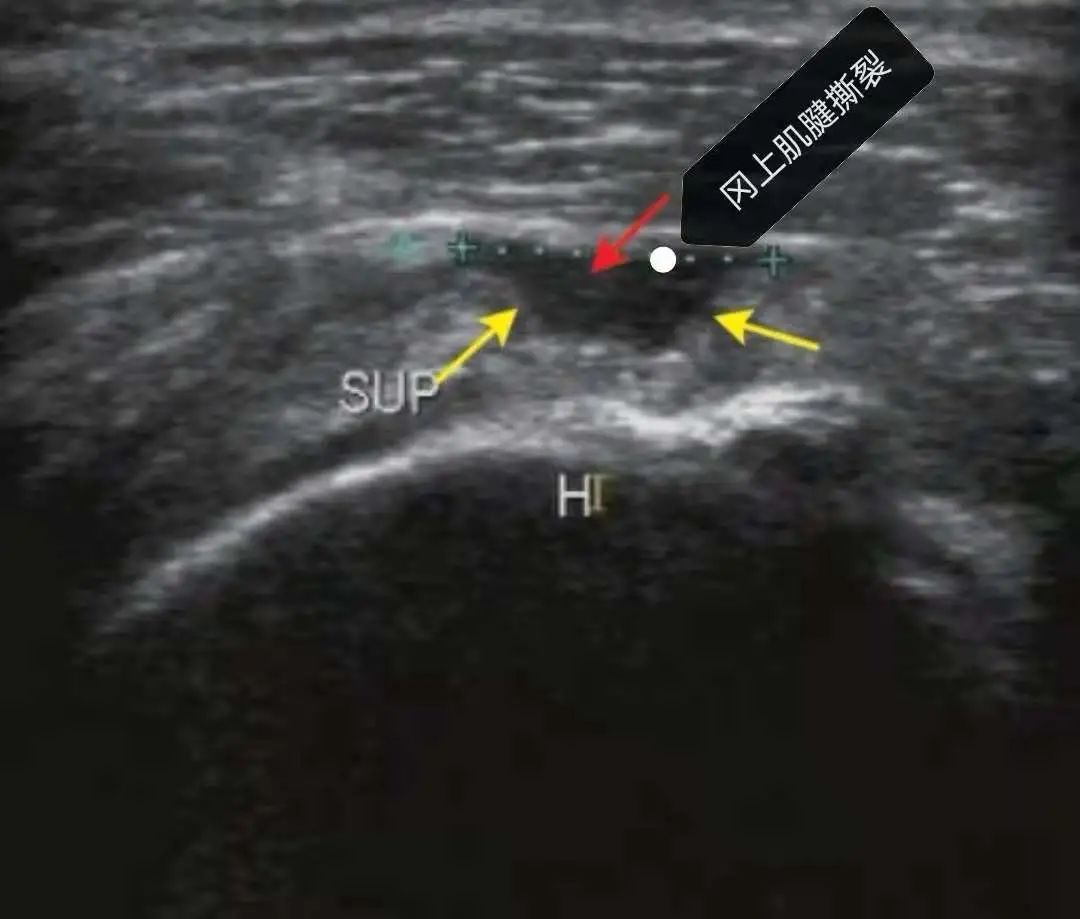

准确率高:如肩袖撕裂与关节镜对比特异性达90%,肌肉、肌腱、韧带、神经部分病变可与MRI媲美!

再打个比方,肩膀痛,除了可以做MRI,肌骨超声也能提供肩袖撕裂情况!

肌肉、肌腱、韧带急、慢性损伤。如:肱二头肌肌腱断裂、肩袖撕裂、距腓前韧带损伤、网球肘、腱鞘炎等。